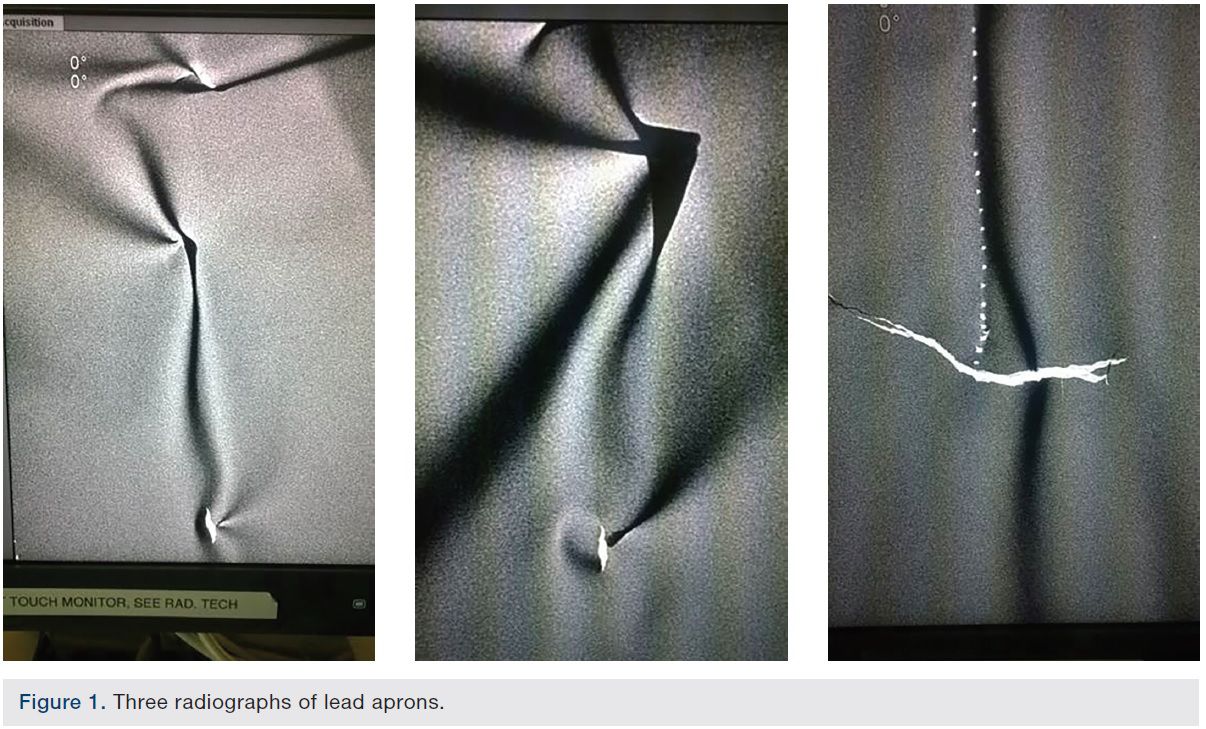

... your lead apron can crack? Underneath the fabric, the sheets of core material can crack and split leaving you vulnerable to radiation.

Cracking usually happens if aprons aren’t stored correctly, but cracks can occur over time to the most immaculately cared for apron.

If an artefact is seen, it is important to ensure it is visualised in the right way.

Often imaging algorithms will accentuate an imperfection to make it look a lot worse than it actually is. We have provided a guide.

Ask your radiation protection officer to arrange for the garment to be screened. Most hospitals have a screening program. This will identify any cracks or tears in the lead.